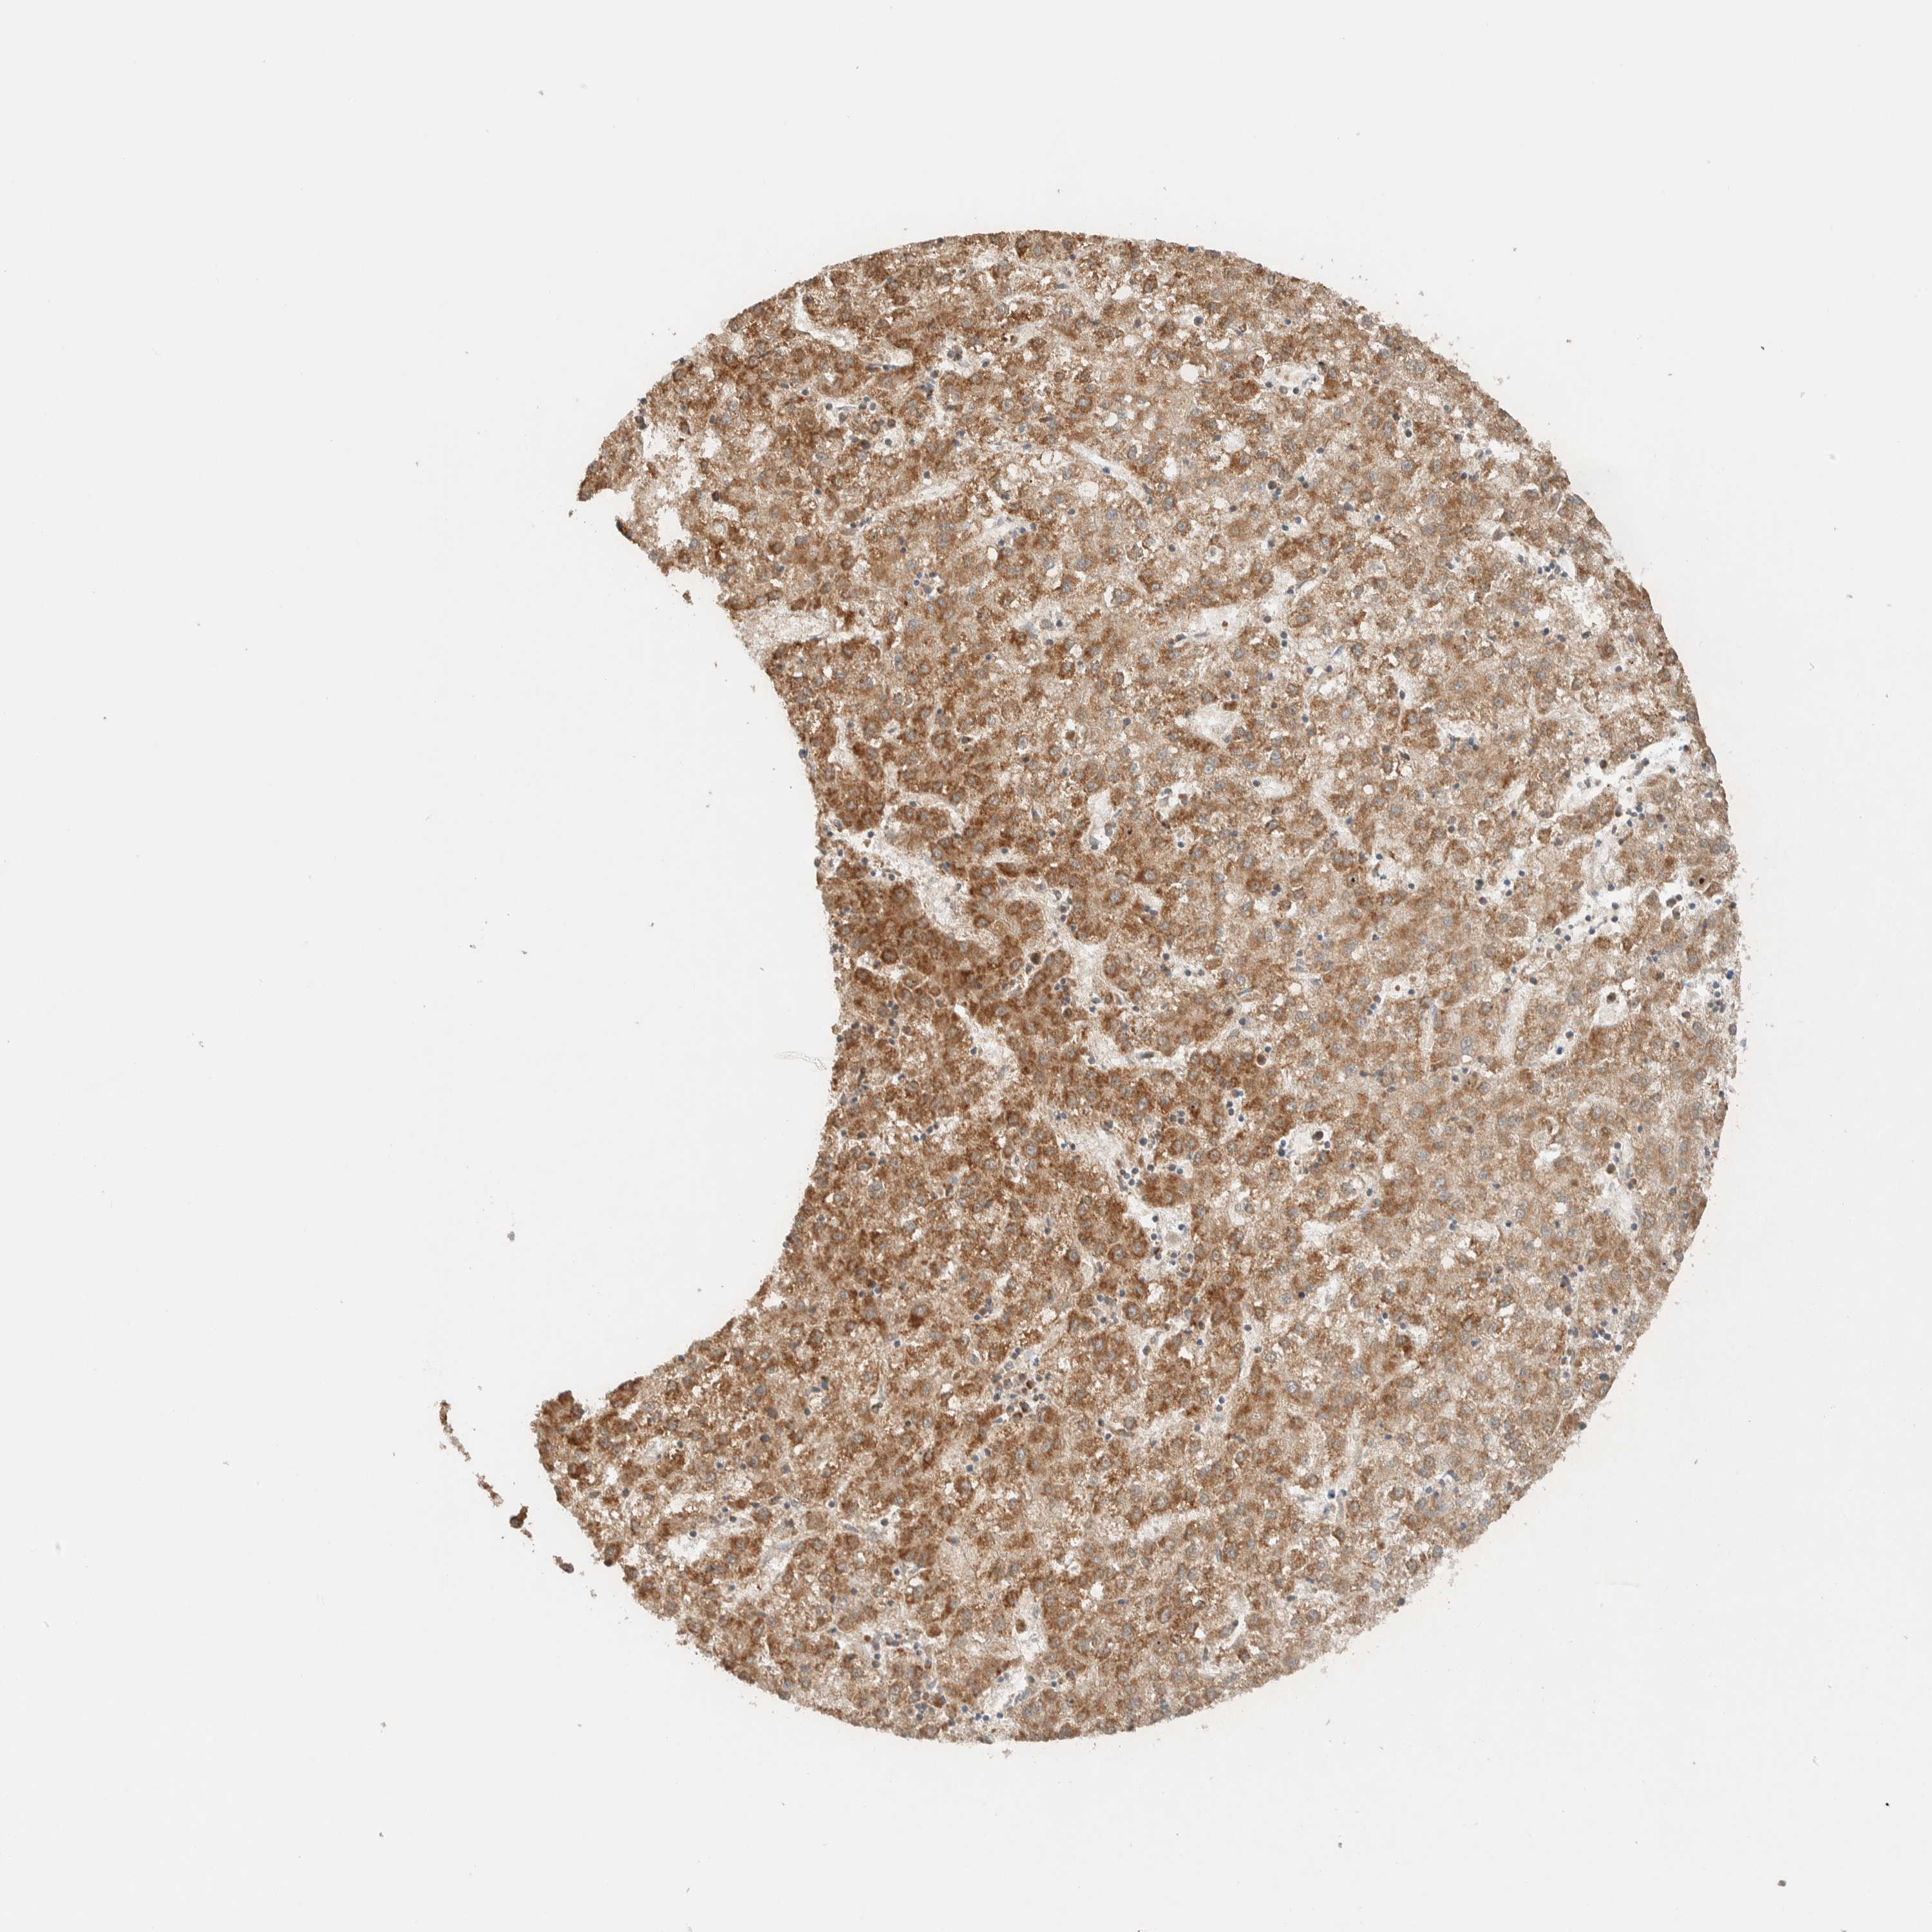

LIVER CANCER - Protein expressioni

A mouse-over function shows sample information and annotation data. Click on an image to view it in a full screen mode. Samples can be filtered based on level of antibody staining by selecting one or several of the following categories: high, medium, low and not detected. The assay and annotation is described here.

Note that samples used for immunohistochemistry by the Human Protein Atlas do not correspond to samples in the TCGA dataset.

Antibody stainingi

Antibody staining in the annotated cell types in the current human tissue is reported as not detected, low, medium, or high, based on conventional immunohistochemistry profiling in selected tissues. This score is based on the combination of the staining intensity and fraction of stained cells.

Each image is clickable and will lead to virtual microscopy that enables deeper exploration of all samples and also displays staining intensity scores, fraction scores and subcellular localization as well as patient and tissue information for each sample.

Antibody HPA024550

Antibody HPA027160

Staining

High

Medium

Low

Not detected

Intensity

Strong

Moderate

Weak

Negative

Quantity

>75%

75%-25%

<25%

None

Location

Nuclear

Cytoplasmic/membranous

Cytoplasmic/membranous,nuclear

Cholangiocarcinoma

Carcinoma, Hepatocellular, NOS